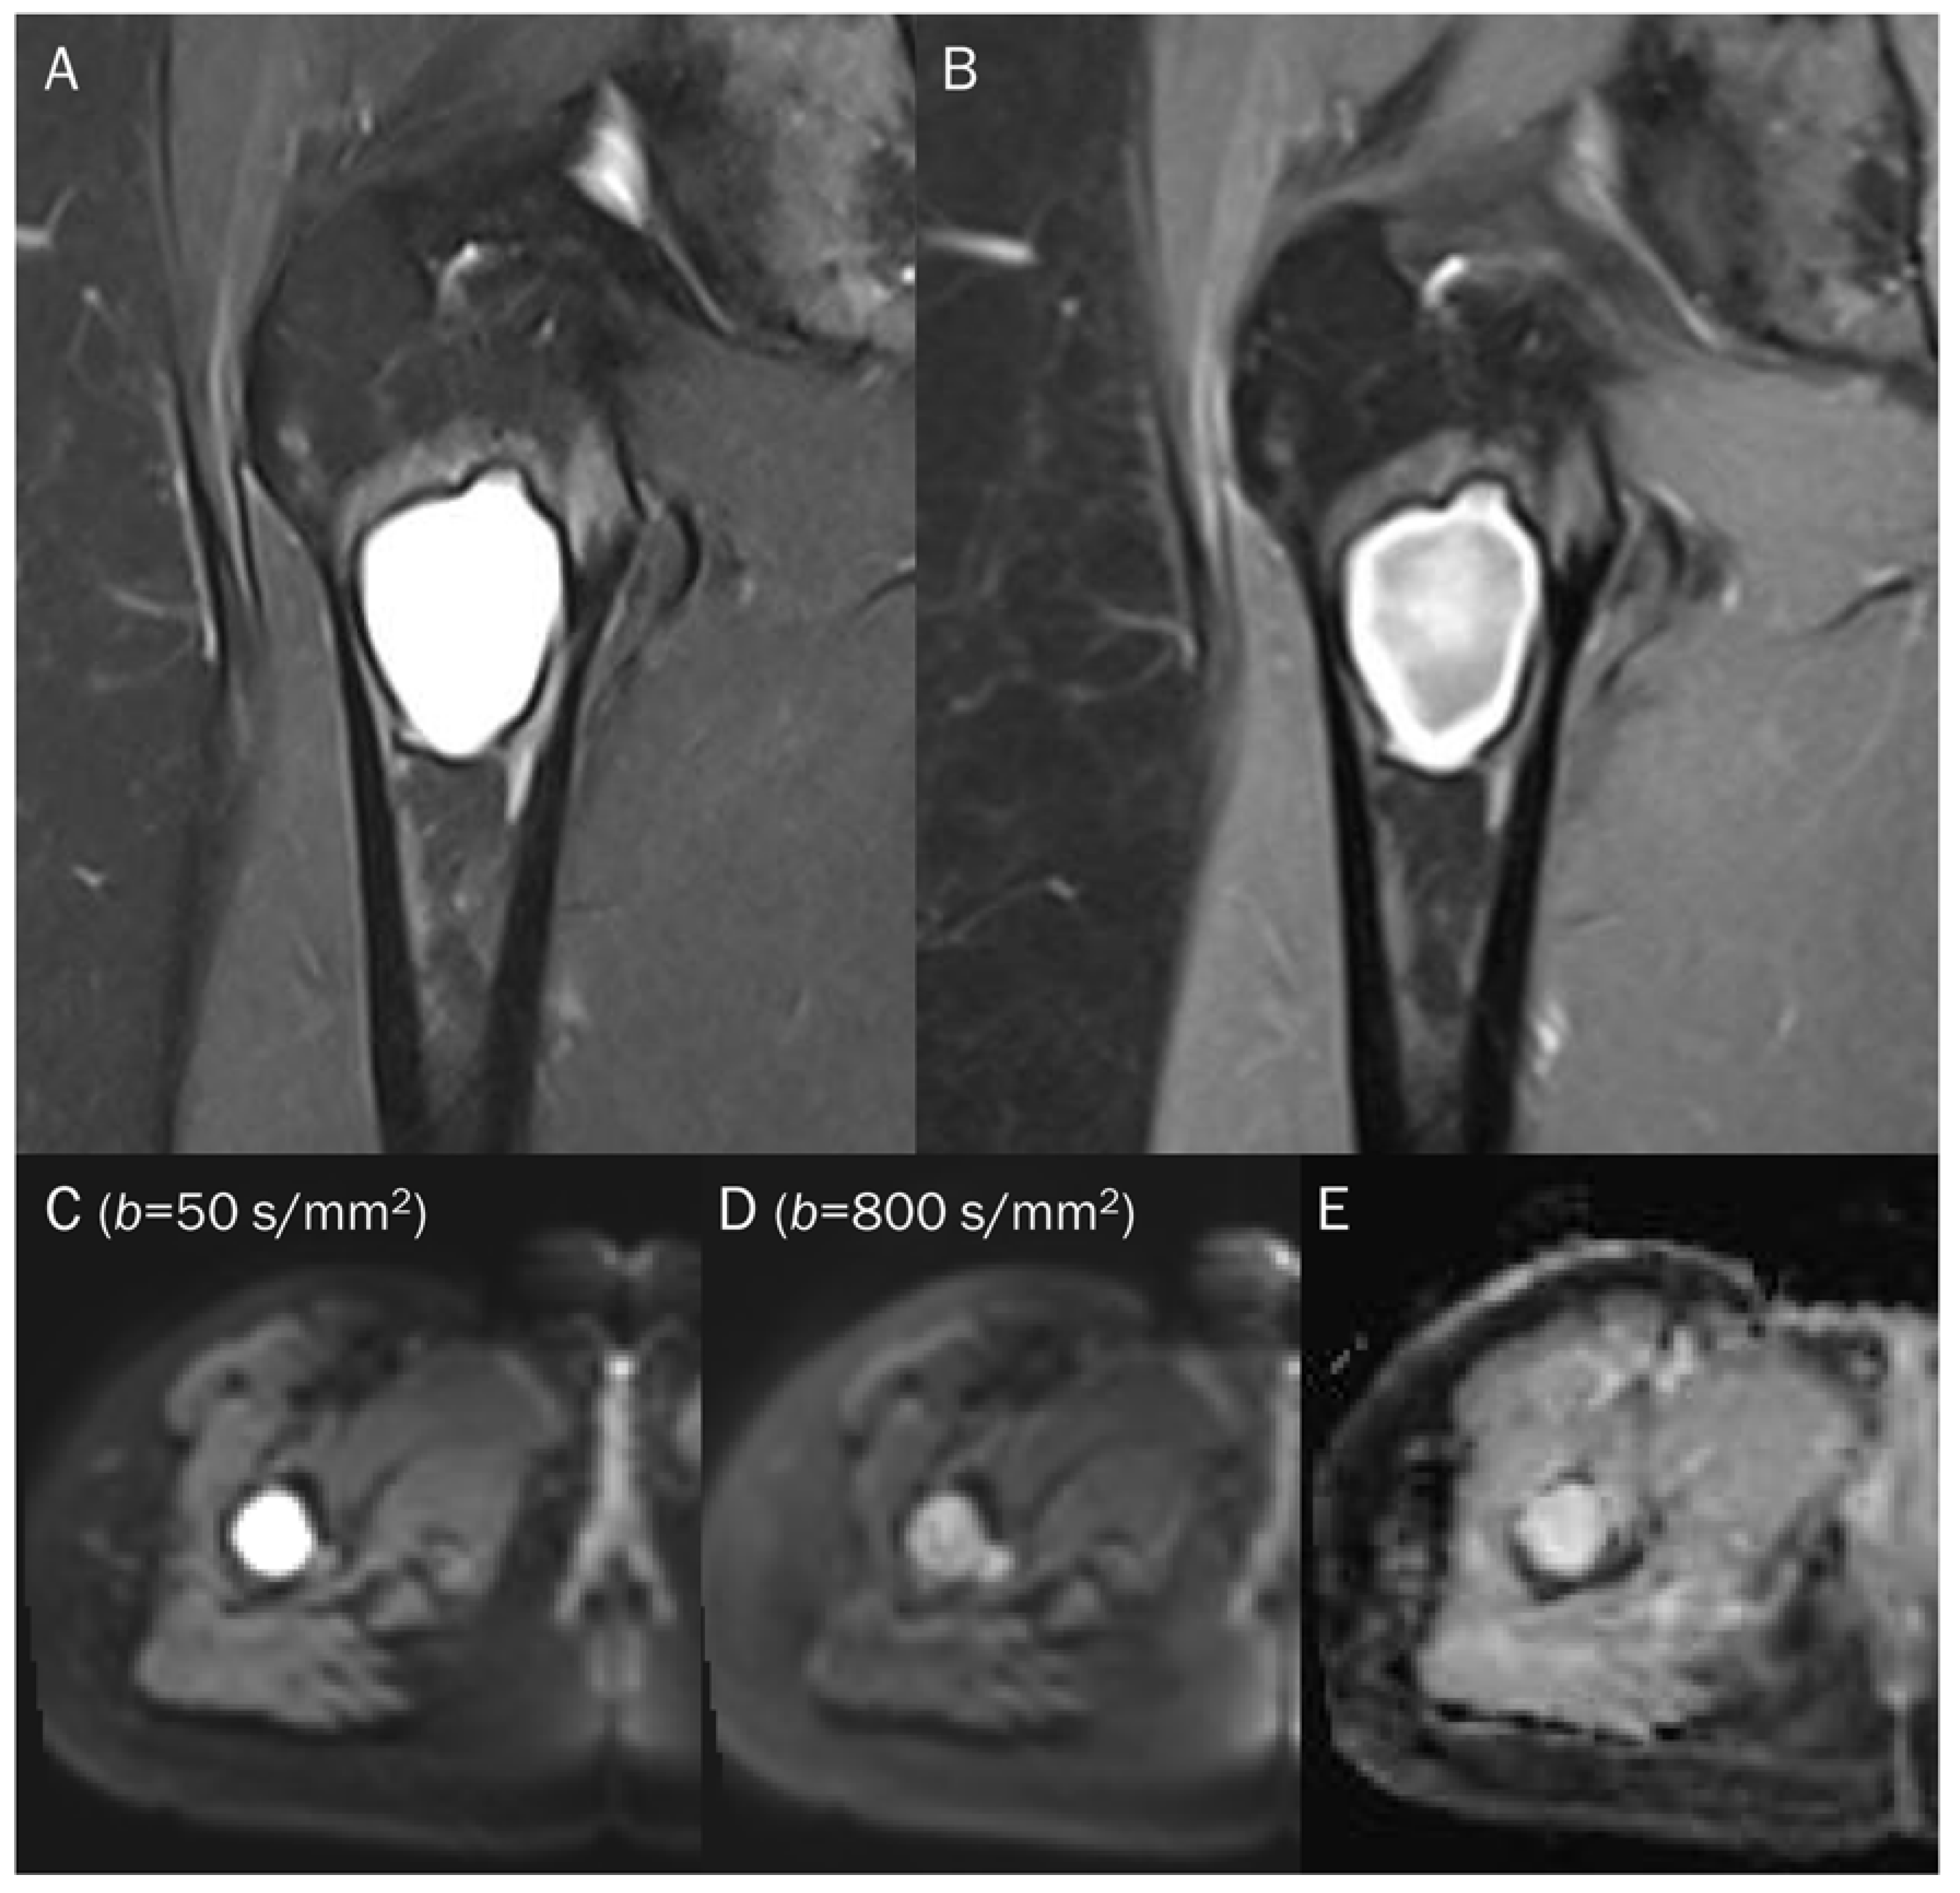

7.2. Hematoma

| Hematoma | ||

| Acute stage | T2 black-out | Deoxyhemoglobin |

| Early subacute stage | T2 black-out | Intracellular methemoglobin |

| Late subacute | Extracellular methemoglobin | 1–4 w | Hyper | Hyper | Hyper | Hypo-to-iso |